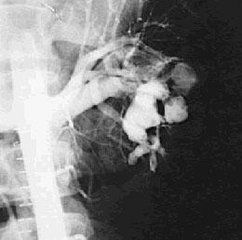

1.都卜勒超聲檢查,是準確而無損傷的方法。2.靜脈腎盂造影,可見腎實質缺損,腎盂有外來壓迫。3.血管造影,可明確診斷。

臨床上根據血尿、蛋白尿、高血壓及上腹部或腎區血管雜音,結合影像學檢查可明確診斷。